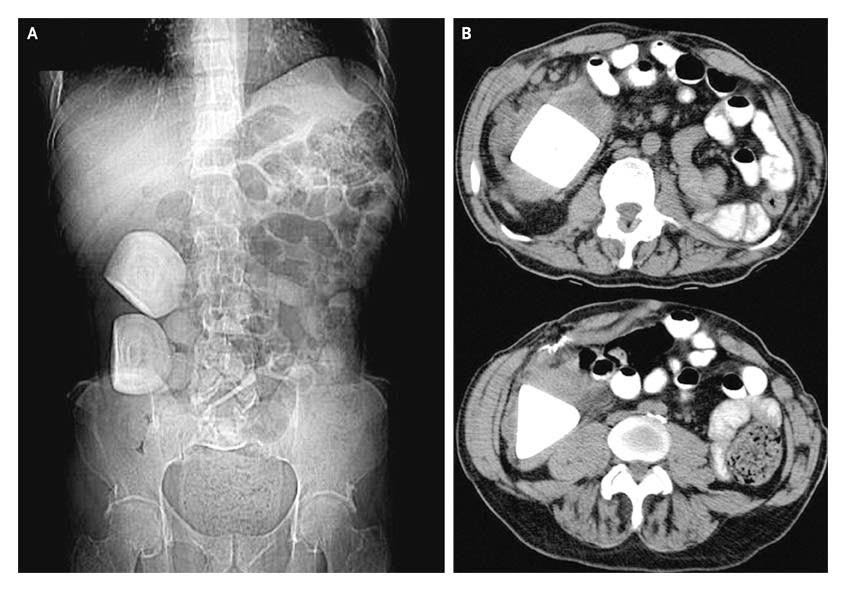

ON RADIOLOGY Calcifications in a Continent Urinary Diversion Indiana Pouch Continent Urinary Diversion a continent urinary diversion gives you more control over urination. The creation of a continent urinary reservoir, or pouch, will mean several things to you. since its creation in 1985 at indiana university, the continent ileocecal reservoir, or indiana pouch, has been a. Both an indiana pouch and a neobladder are examples of continent. It involves either a. Indiana Pouch Continent Urinary Diversion.